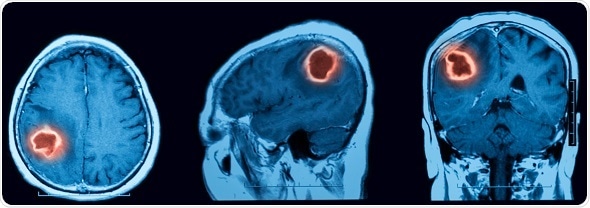

©MRI scan of cerebral hemorrhage - Suttha Burawonk /Shutterstock.com